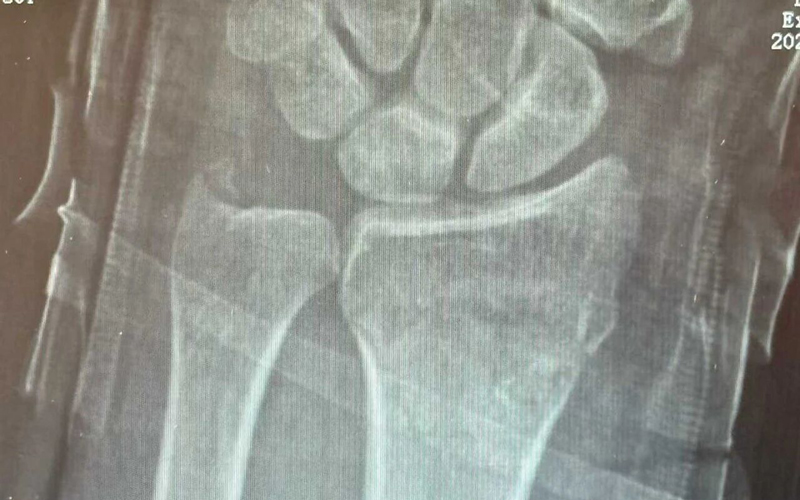

洗菜摔伤治疗前后对比

厕所摔伤治疗前后对比